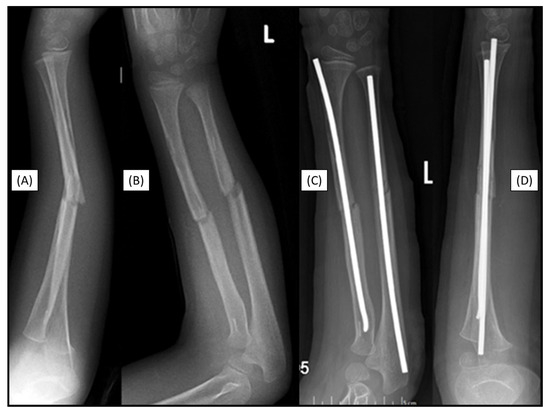

3.7. Case 7: Recurrent Fracture